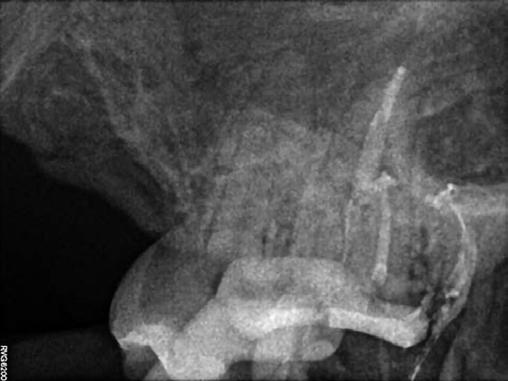

Gyökéramputációt főként a furkáció érintett nagyőrlő fogak ellátása során szoktunk alkalmazni. Derks és mtsai. vizsgálatában a gyökéramputált nagyőrlő fogak közel 80%-a 20 évvel a beavatkozás elvégzését követően is megtartott volt. 1998 októberében egy 39 éves férfi páciens a jobb alsó kvadránsban jelentkező ínyérzékenység miatt kereste fel rendelőnket. A klinikai vizsgálat során jobb alsó első és második nagyőrlő fog között (46–47) nagy kiterjedésű csontveszteséget észleltünk. Ettől eltekintve a teljes fogazat parodontális státusza megfelelőnek bizonyult. A jobb alsó kvadránsban végzett szenzibilitás vizsgálat során arra az eredménye jutottunk, hogy a 46-os fog vélelmezhetően elhalt (10. ábra).

A páciens beleegyezését követően a 46-os fog disztális gyökere, a disztális gyökér felett lévő koronális rész megőrzése mellett rezekcióra került (11. ábra). A rezekciót követően a referáló orvos a 46. és 47. fogak koronáját Ribbond szalag és kompozit segítségével egymáshoz rögzítette. A sebészi beavatkozást követően 22 évvel készült kontrollfelvételen a lézió csontos telődése, kortikális csontállomány kialakulása, valamint a furkáció körüli csontos regeneráció volt megfigyelhető (12. ábra) A károsodott fogak megtartására szolgáló lehetőségek fejlődésének, valamint az implantátumok behelyezésével kapcsolatos rizikófaktorok jobb megértésének köszönhetően ma már más szemmel vizsgáljuk a fogak eltávolításának szükségességét. A kérdéses prognózissal vagy a kis protetikai értékkel rendelkező fogak eltávolítása előtt mindig érdemes felmérni az ezzel elérhető lehetséges előnyök nagyságát. A kemény- és lágyszöveti pótlás lehetőségeinek fejlődésével, a PRF elérhetőségével, a minimálinvazív sebészeti módszerek és az operációs mikroszkópok elterjedésével, valamint a varróanyagok és varrat technikák egyre kifinomultabbá válásával ma már alaposan el kell gondolkodnunk az előtt, hogy egy fogat egy implantátum behelyezése érdekében eltávolítsunk. Mára sokkal kedvezőbb prognózist és sokkal nagyobb sikerességet tudunk elérni a korábban menthetetlennek gondolt fogak kezelése során.